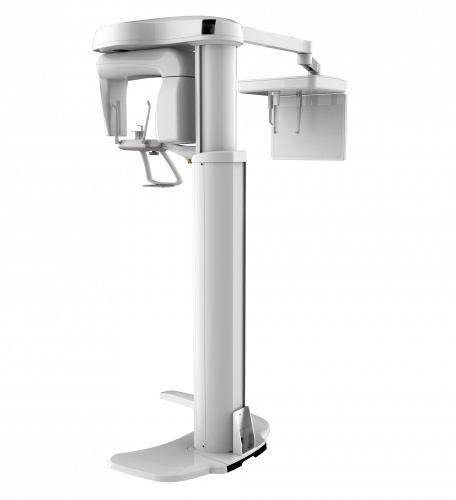

Drag the product with your mouse or fingers; or click on the feature from the list.

The PaX-i provides precise high-quality panoramic image by combining image processing and accumulated experience in dental imaging from VATECH. This will improve your diagnostic accuracy by increasing treatment planning and patient satisfaction.

| TYPE | PANO | CEPH (SCAN) | CEPH (Rapid) |

|---|---|---|---|

| PaX-i | | | |

| PaX-i SC | | | |

| FUNCTION | SCAN TIME | FOCAL SPOT | TUBE VOLTAGE/CURRENT |

|---|---|---|---|

| Pano + Ceph | Pano : HD 13.5 sec/ Normal 10.1 sec Ceph : Scan 12.9 sec |

0.5 mm | 50-90 kVp/ 4-10 mA |

| CEPH FOV SIZE | GRAY SCALE | PATIENT POSITIONING |

|---|---|---|

|

SC 8.3” x 9.1” [LAT, PA, SMV, Waters View, Carpus]

10.6” x 9.1” [Full LAT] |

14 bit | Standing / Wheelchair Accessible |

| TYPE | TOP VIEW | FRONT VIEW |

|---|---|---|

|

PaX-i (Pano) |

|

|

|

PaX-i SC (Pano/Scan Ceph) |

|

|